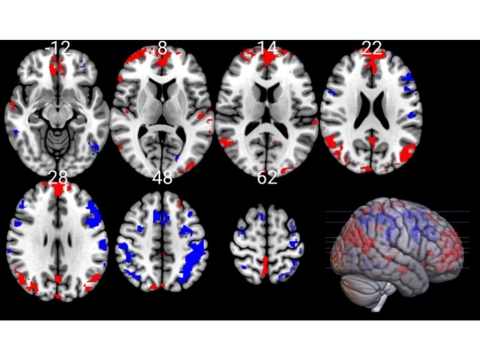

MRI scan of the brain showing the parietal cortex (left) and medial prefrontal cortex (right) as red after a cold water bath - indicating increased activity compared to the areas showing in blue

Comparing the scans showed that changes had occurred in the connectivity between specific parts of the brain, in particular, the medial prefrontal cortex and the parietal cortex.

“These are the parts of the brain that control our emotions, and help us stay attentive and make decisions,” Dr Yankouskaya said. “So when the participants told us that they felt more alert, excited and generally better after their cold bath, we expected to see changes to the connectivity between those parts. And that is exactly what we found.”